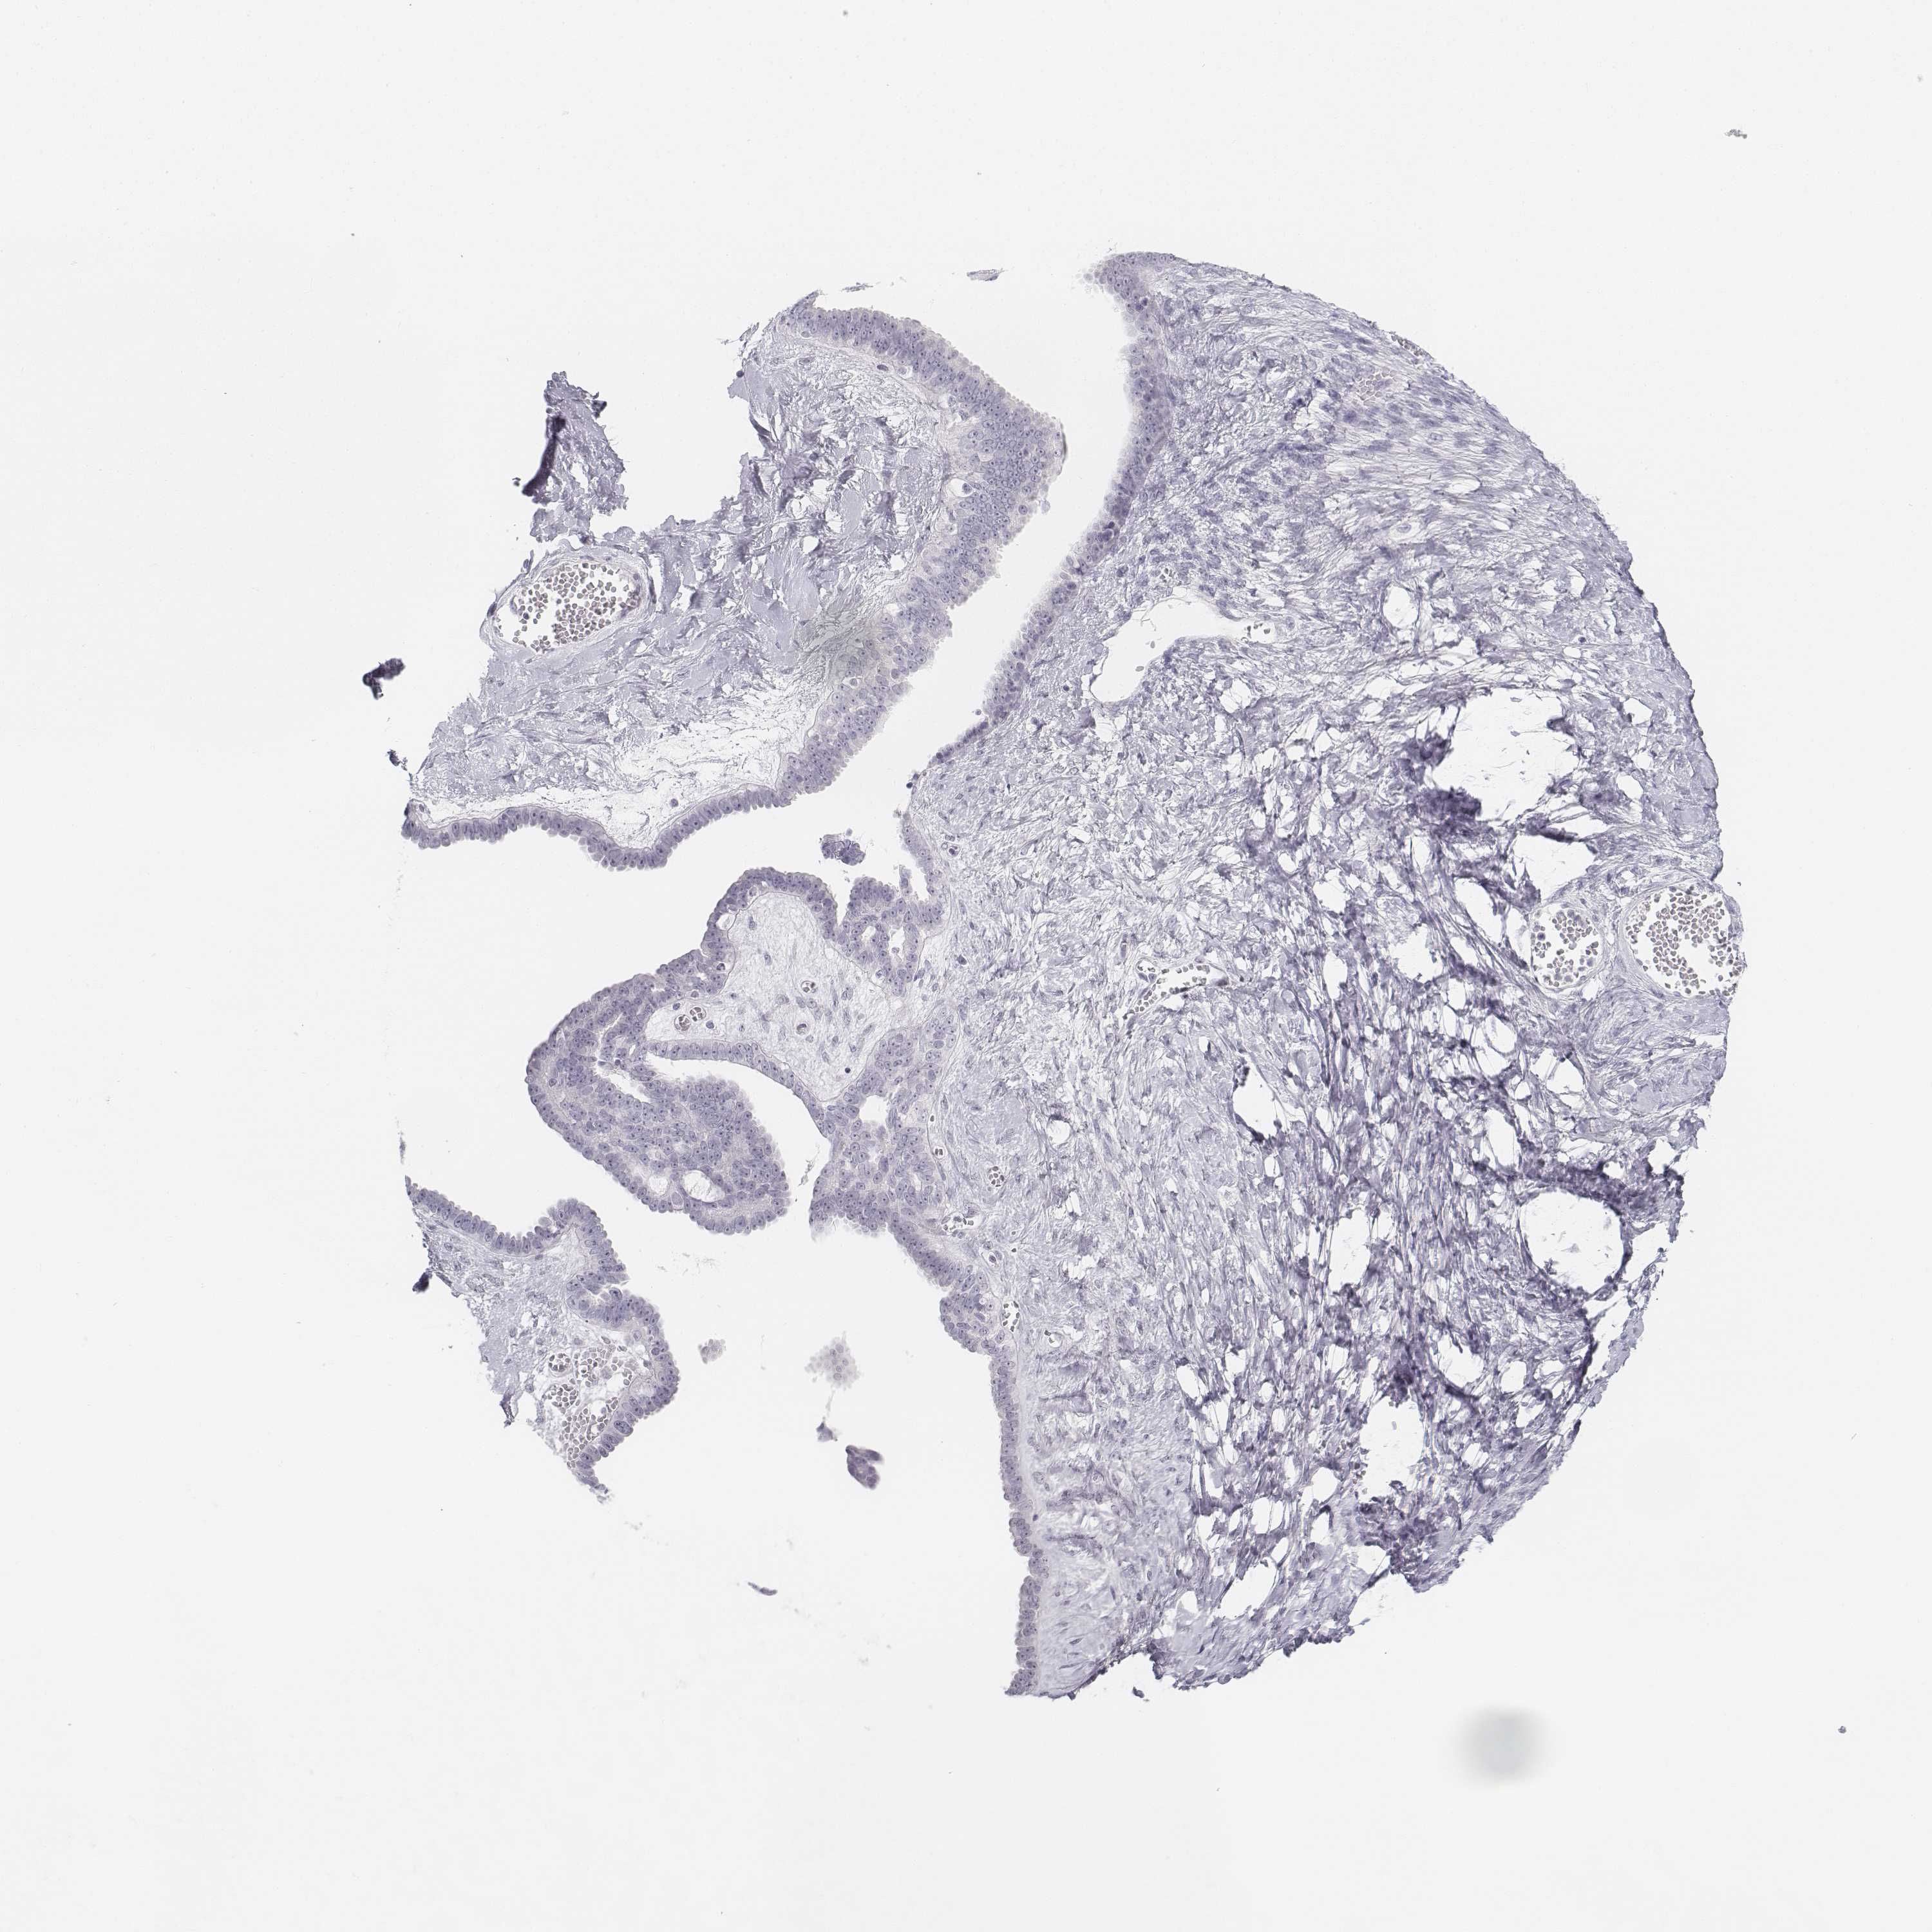

OVARIAN CANCER - Protein expressioni

A mouse-over function shows sample information and annotation data. Click on an image to view it in a full screen mode. Samples can be filtered based on level of antibody staining by selecting one or several of the following categories: high, medium, low and not detected. The assay and annotation is described here.

Note that samples used for immunohistochemistry by the Human Protein Atlas do not correspond to samples in the TCGA dataset.

Antibody stainingi

Antibody staining in the annotated cell types in the current human tissue is reported as not detected, low, medium, or high, based on conventional immunohistochemistry profiling in selected tissues. This score is based on the combination of the staining intensity and fraction of stained cells.

Each image is clickable and will lead to virtual microscopy that enables deeper exploration of all samples and also displays staining intensity scores, fraction scores and subcellular localization as well as patient and tissue information for each sample.

Antibody HPA053977

Antibody HPA058943

Cystadenocarcinoma, serous, NOS

Cystadenocarcinoma, mucinous, NOS

Carcinoma, endometroid